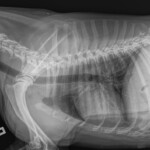

The Whyalla Veterinary Clinic has a new Shimadzu MUX10 Xray machine for high quality radiographs and a new Agfa XD14 Csi Tethered panel to produce outstanding direct digital Xrays from the images from the Shimadzu MUX10 Xray machine.

The XD14 CsI Tethered Panel is an integral part of an Agfa HealthCare’s Instant DR solution, which includes the NX image acquisition software with MUSICA3 processing and detector. These cassette-less and filmless solutions provide a range of workflow benefits that improve quality, productivity and speed up exam time.